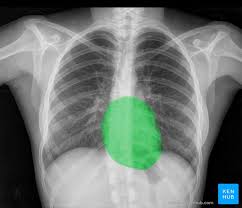

It is often the first imaging test a doctor will order if lung or heart disease is suspected. Each subtype of throat cancer has its own criteria for each stage. The bone at the site of the cancer may look ragged instead of solid. The appearance of throat cancer on the other hand depends on the part of the throat that is affected by cancer and the stage of its development. To evaluate respiratory conditions like asthma, bronchitis, and pneumonia, heart conditions, broken ribs, and to look for fluid and tumors within the chest cavity.

The appearance of throat cancer on the other hand depends on the part of the throat that is affected by cancer and the stage of its development. Lung cancer tumors look like white round circles on cxr. Later stages indicate more advanced cancer, with stage iv being the most advanced. For instance, voice changes may be a sign of laryngeal (voice box) cancer, but they would rarely indicate cancer of the pharynx. Your voice box sits just below your throat and also is susceptible to throat cancer. Let's talk about throat cancer. This mass will look like a white spot on your lungs, while the lung itself will appear black. Sometimes doctors can see a tumor around the defect in the bone that might extend into nearby tissues (such as muscle. If they notice signs of a problem, they'll look carefully inside your mouth and throat, sometimes with a special lighted tool, and may feel your jaw and neck for lumps or patches. Lung cancer and throat cancer sometimes occur at the same time. The most sensitive way to detect throat cancer is to have an. The leukoplakia is apparent under imaging test and cannot be rubbed off. The most common symptom of thyroid cancer is a hard lump on the neck—but most patients experience no symptoms at all.

Prior to testing, the table will glide into the tunnel where it remains in position until testing is completed. Lung cancer tumors look like white round circles on cxr. Lung cancer and throat cancer sometimes occur at the same time. If the fna doesn't show cancer, it only means that cancer was not found in that lymph node. Let's talk about throat cancer. It is often the first imaging test a doctor will order if lung or heart disease is suspected. Ultrasound is useful in a few instances. More stories you might like. I had an on and off sore throat and hoarseness for many many months, but was a smoker. Throat cancer refers cancer that develops in your throat (pharynx) or voice box (larynx). The tumor may extend into other bone tissue nearby like muscle or fat. Ameloblastoma isn't the same as jaw cancer or mouth cancer, head and neck cancer, nor even a bone cancer. There could still be cancer in other places.